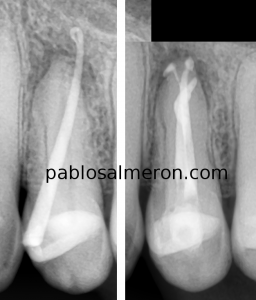

This case was referred to me for the retreatment o This case was referred to me for the retreatment of a lower incisor (#41). The tooth presented with a big chronic apical periodontitis, which seemed to be affecting the teeth next to it as well.

In this kind of situation, it is very important to do a meticulous diagnosis to identify the source of the problem so that we do not treat the other teeth mistakenly without reason.

The large size of the lesion is not a synonym for tooth extraction, which unfortunately we see quite often in the decision-making processes. In the absence of bacteria, the bone heals, and we can save the tooth.

The retreatment was carried out over two sessions with a three-week calcium hydroxide dressing between them.

The use of advanced technologies, materials, and techniques is crucial for improving treatment success rates. With the right experience, planning, and tools, complex cases are usually successful. I always recommend seeking out a specialist with experience to address these kinds of situations and prevent further damage. While results may vary from patient to patient, they are highly predictable in the vast majority of cases.